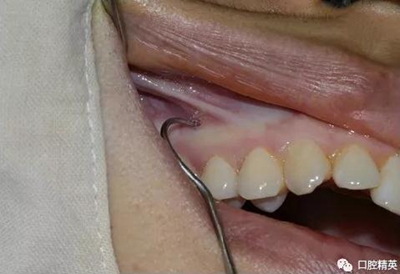

先使用刀背劃一垂直于頜骨矢狀平面的印記,以確定種植釘?shù)慕h(yuǎn)中位置。

常用11號(hào)尖刀片劃一個(gè)小切口,切開(kāi)粘骨膜,牙科小挖匙分離粘骨膜。

再次,植入微型種植體,在附著牙齦處不需要粘骨膜翻瓣,在牙槽黏膜處則需要切開(kāi)黏膜以避免植入時(shí)軟組織被卷入,植入部位通常在膜齦結(jié)合部位或偏根方2~3mm,植入角度與骨面垂直并傾斜15~20度,即向根尖方向植入,術(shù)后拍根尖片以確認(rèn)與牙根的關(guān)系。術(shù)后口服抗生素預(yù)防感染并進(jìn)行口腔衛(wèi)生宣教。